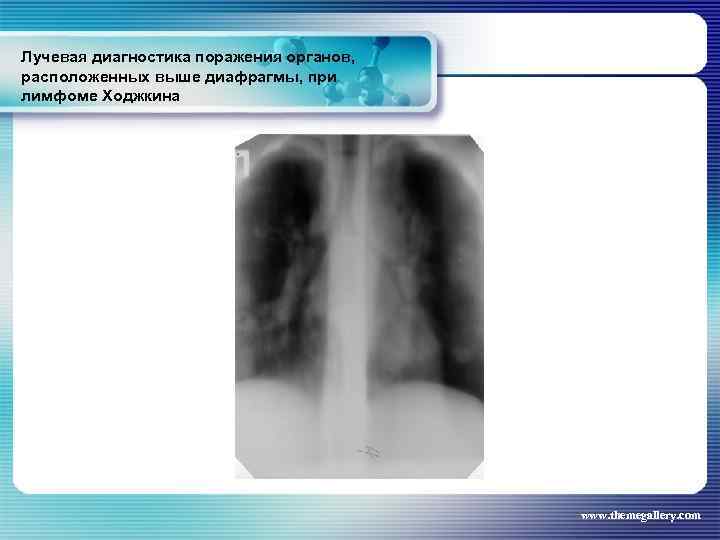

Лучевая диагностика поражения органов, расположенных выше диафрагмы, при лимфоме Ходжкина Частота поражения органов грудной полости при лимфоме Ходжкина: поражение средостения легких плевры грудной стенки - 66, 7 % 33, 75% 5, 3% 1, 8% www. themegallery. com

Лучевая диагностика поражения органов, расположенных выше диафрагмы, при лимфоме Ходжкина Частота поражения органов грудной полости при лимфоме Ходжкина: поражение средостения легких плевры грудной стенки - 66, 7 % 33, 75% 5, 3% 1, 8% www. themegallery. com

Лучевая диагностика поражения органов, расположенных выше диафрагмы, при лимфоме Ходжкина www. themegallery. com

Лучевая диагностика поражения органов, расположенных выше диафрагмы, при лимфоме Ходжкина www. themegallery. com

Лучевая диагностика поражения органов, расположенных выше диафрагмы, при лимфоме Ходжкина www. themegallery. com

Лучевая диагностика поражения органов, расположенных выше диафрагмы, при лимфоме Ходжкина www. themegallery. com

Лучевая диагностика поражения органов, расположенных выше диафрагмы, при лимфоме Ходжкина www. themegallery. com

Лучевая диагностика поражения органов, расположенных выше диафрагмы, при лимфоме Ходжкина www. themegallery. com

Лучевая диагностика поражения органов, расположенных выше диафрагмы, при лимфоме Ходжкина www. themegallery. com

Лучевая диагностика поражения органов, расположенных выше диафрагмы, при лимфоме Ходжкина www. themegallery. com

Лучевая диагностика поражения органов, расположенных выше диафрагмы, при лимфоме Ходжкина www. themegallery. com

Лучевая диагностика поражения органов, расположенных выше диафрагмы, при лимфоме Ходжкина www. themegallery. com

Лучевая диагностика поражения органов, расположенных выше диафрагмы, при лимфоме Ходжкина www. themegallery. com

Лучевая диагностика поражения органов, расположенных выше диафрагмы, при лимфоме Ходжкина www. themegallery. com

Лучевая диагностика поражения органов, расположенных выше диафрагмы, при лимфоме Ходжкина www. themegallery. com

Лучевая диагностика поражения органов, расположенных выше диафрагмы, при лимфоме Ходжкина www. themegallery. com

Лучевая диагностика поражения органов, расположенных выше диафрагмы, при лимфоме Ходжкина www. themegallery. com

Лучевая диагностика поражения органов, расположенных выше диафрагмы, при лимфоме Ходжкина www. themegallery. com

Лучевая диагностика поражения органов, расположенных выше диафрагмы, при лимфоме Ходжкина www. themegallery. com

Лучевая диагностика поражения органов, расположенных выше диафрагмы, при лимфоме Ходжкина www. themegallery. com

Лучевая диагностика поражения органов, расположенных выше диафрагмы, при лимфоме Ходжкина www. themegallery. com

Лучевая диагностика поражения органов, расположенных выше диафрагмы, при лимфоме Ходжкина www. themegallery. com

Лучевая диагностика поражения органов, расположенных выше диафрагмы, при лимфоме Ходжкина www. themegallery. com

Лучевая диагностика поражения органов, расположенных выше диафрагмы, при лимфоме Ходжкина www. themegallery. com

Лучевая диагностика поражения органов, расположенных выше диафрагмы, при лимфоме Ходжкина www. themegallery. com

Лучевая диагностика поражения органов, расположенных выше диафрагмы, при лимфоме Ходжкина www. themegallery. com